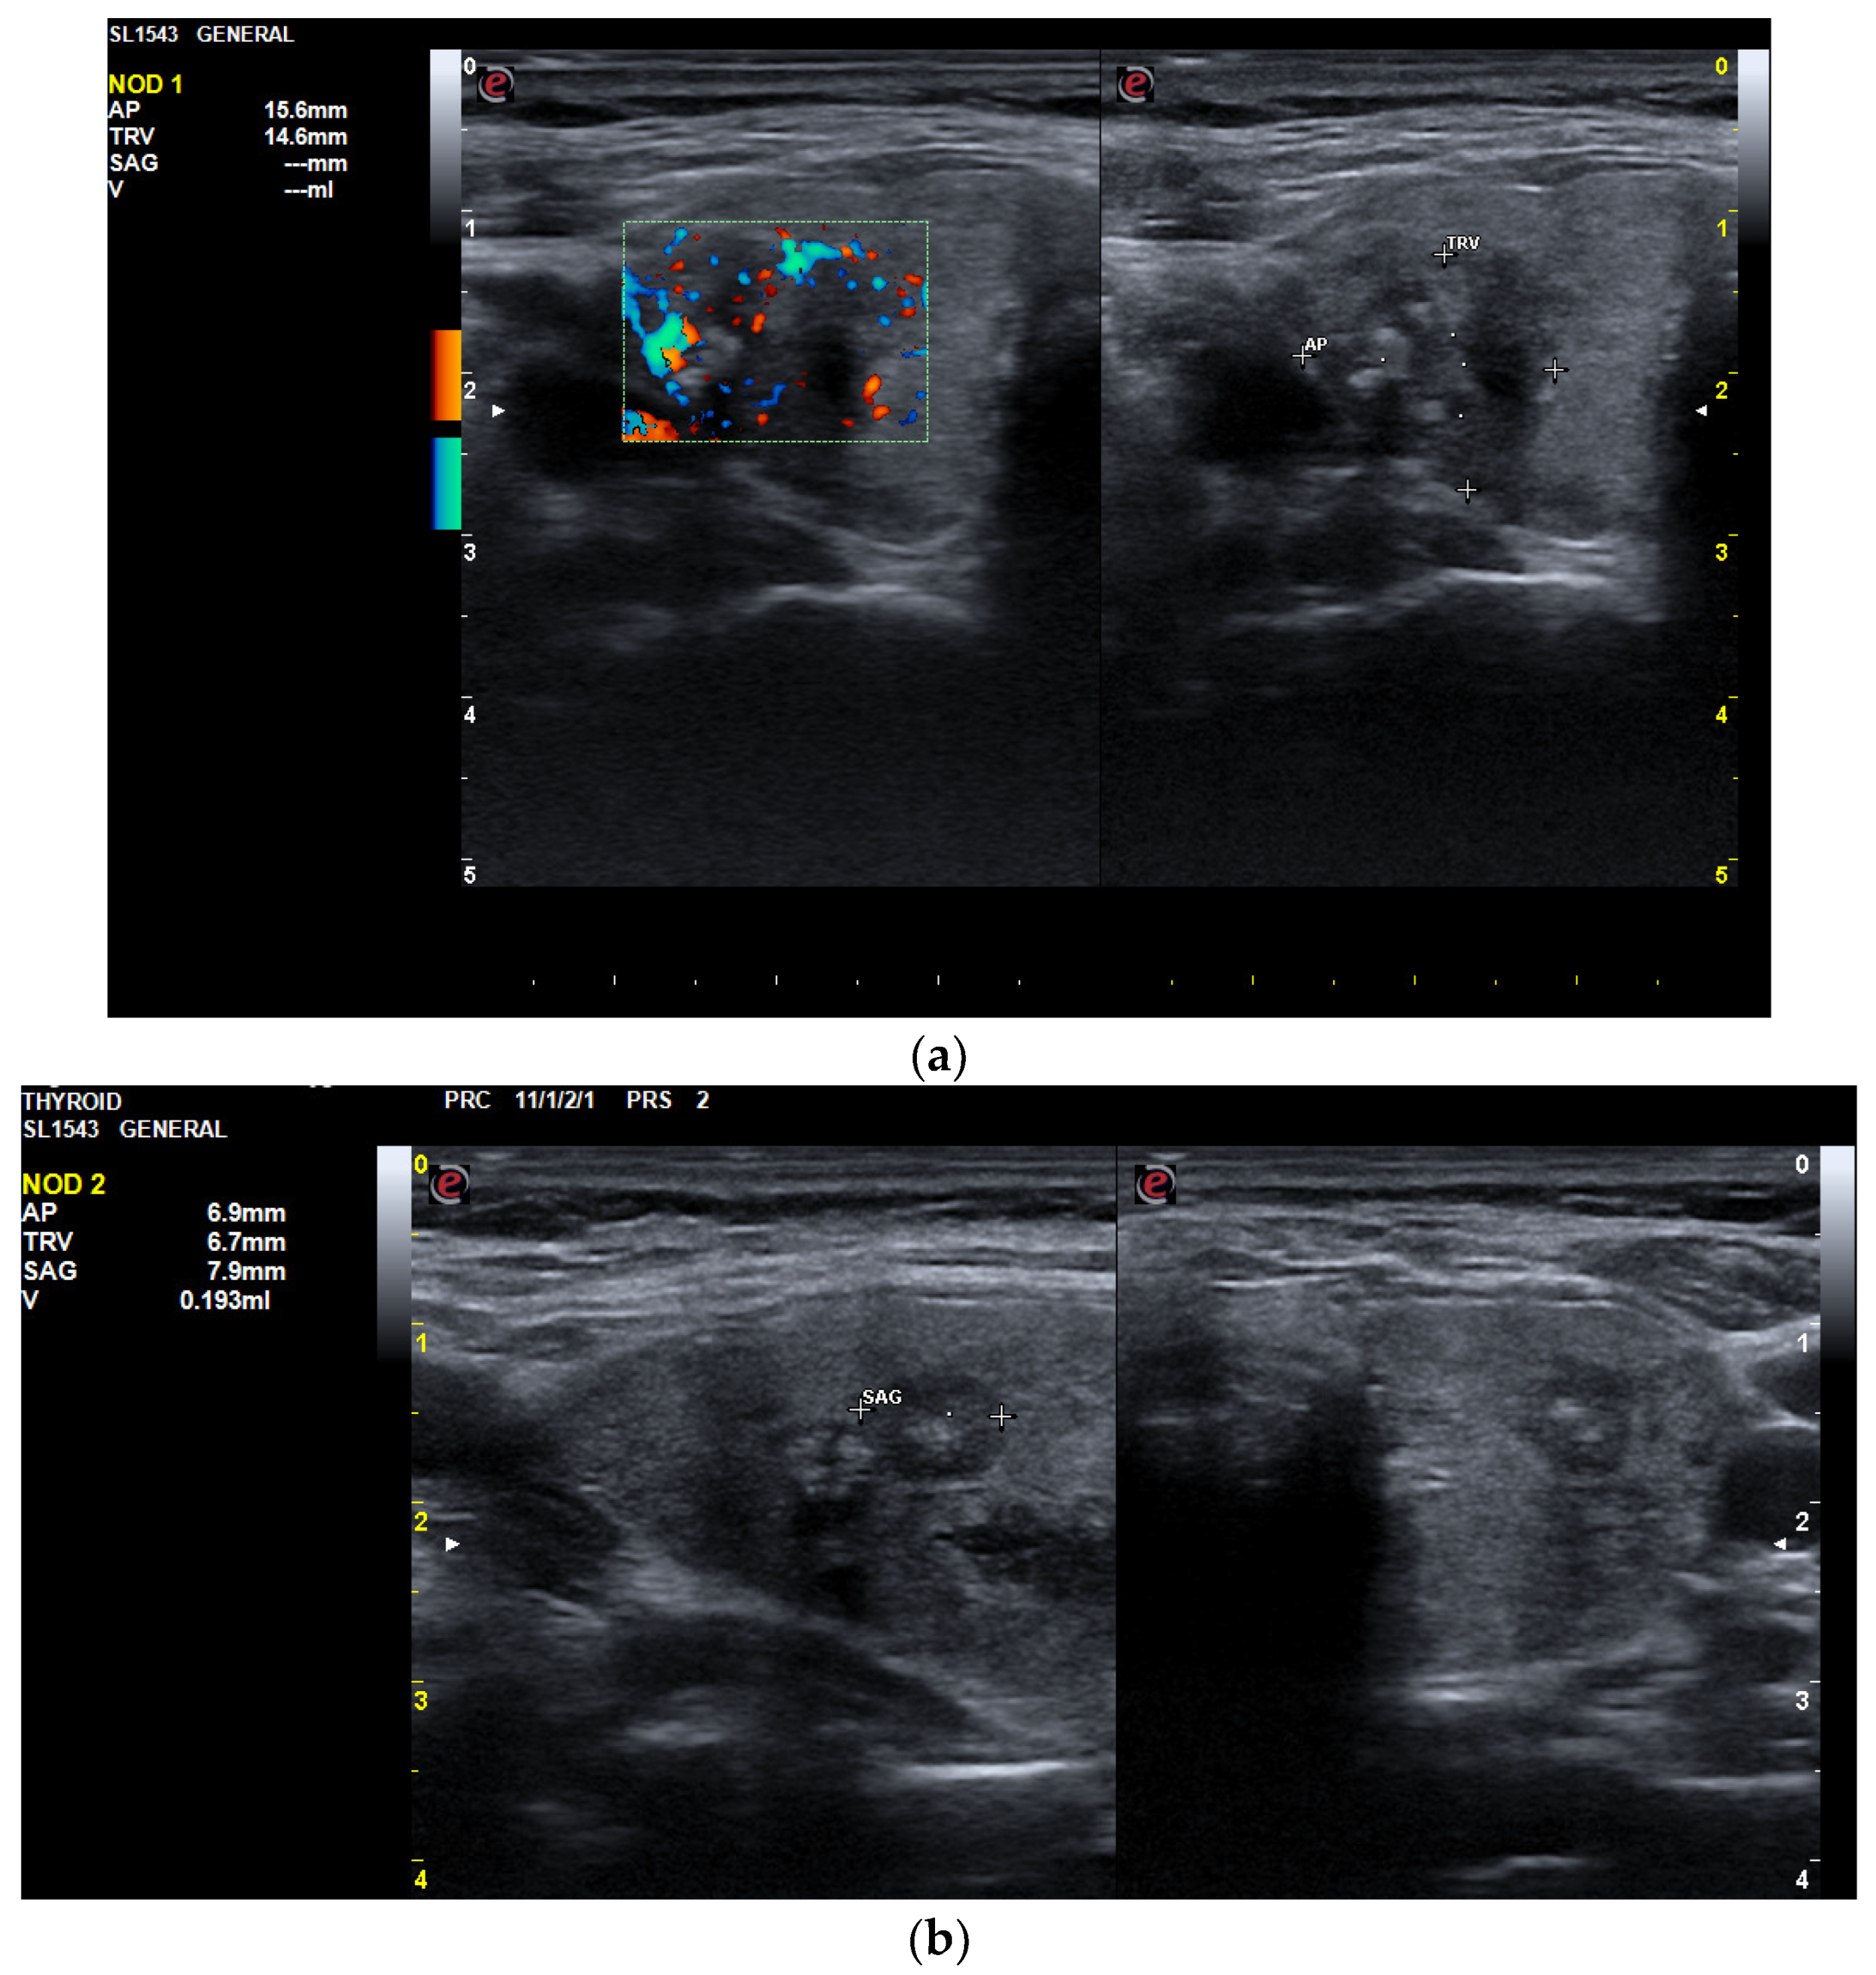

3.1.2. Thyroid Ultrasound

3.2.2. Thyroid Ultrasound